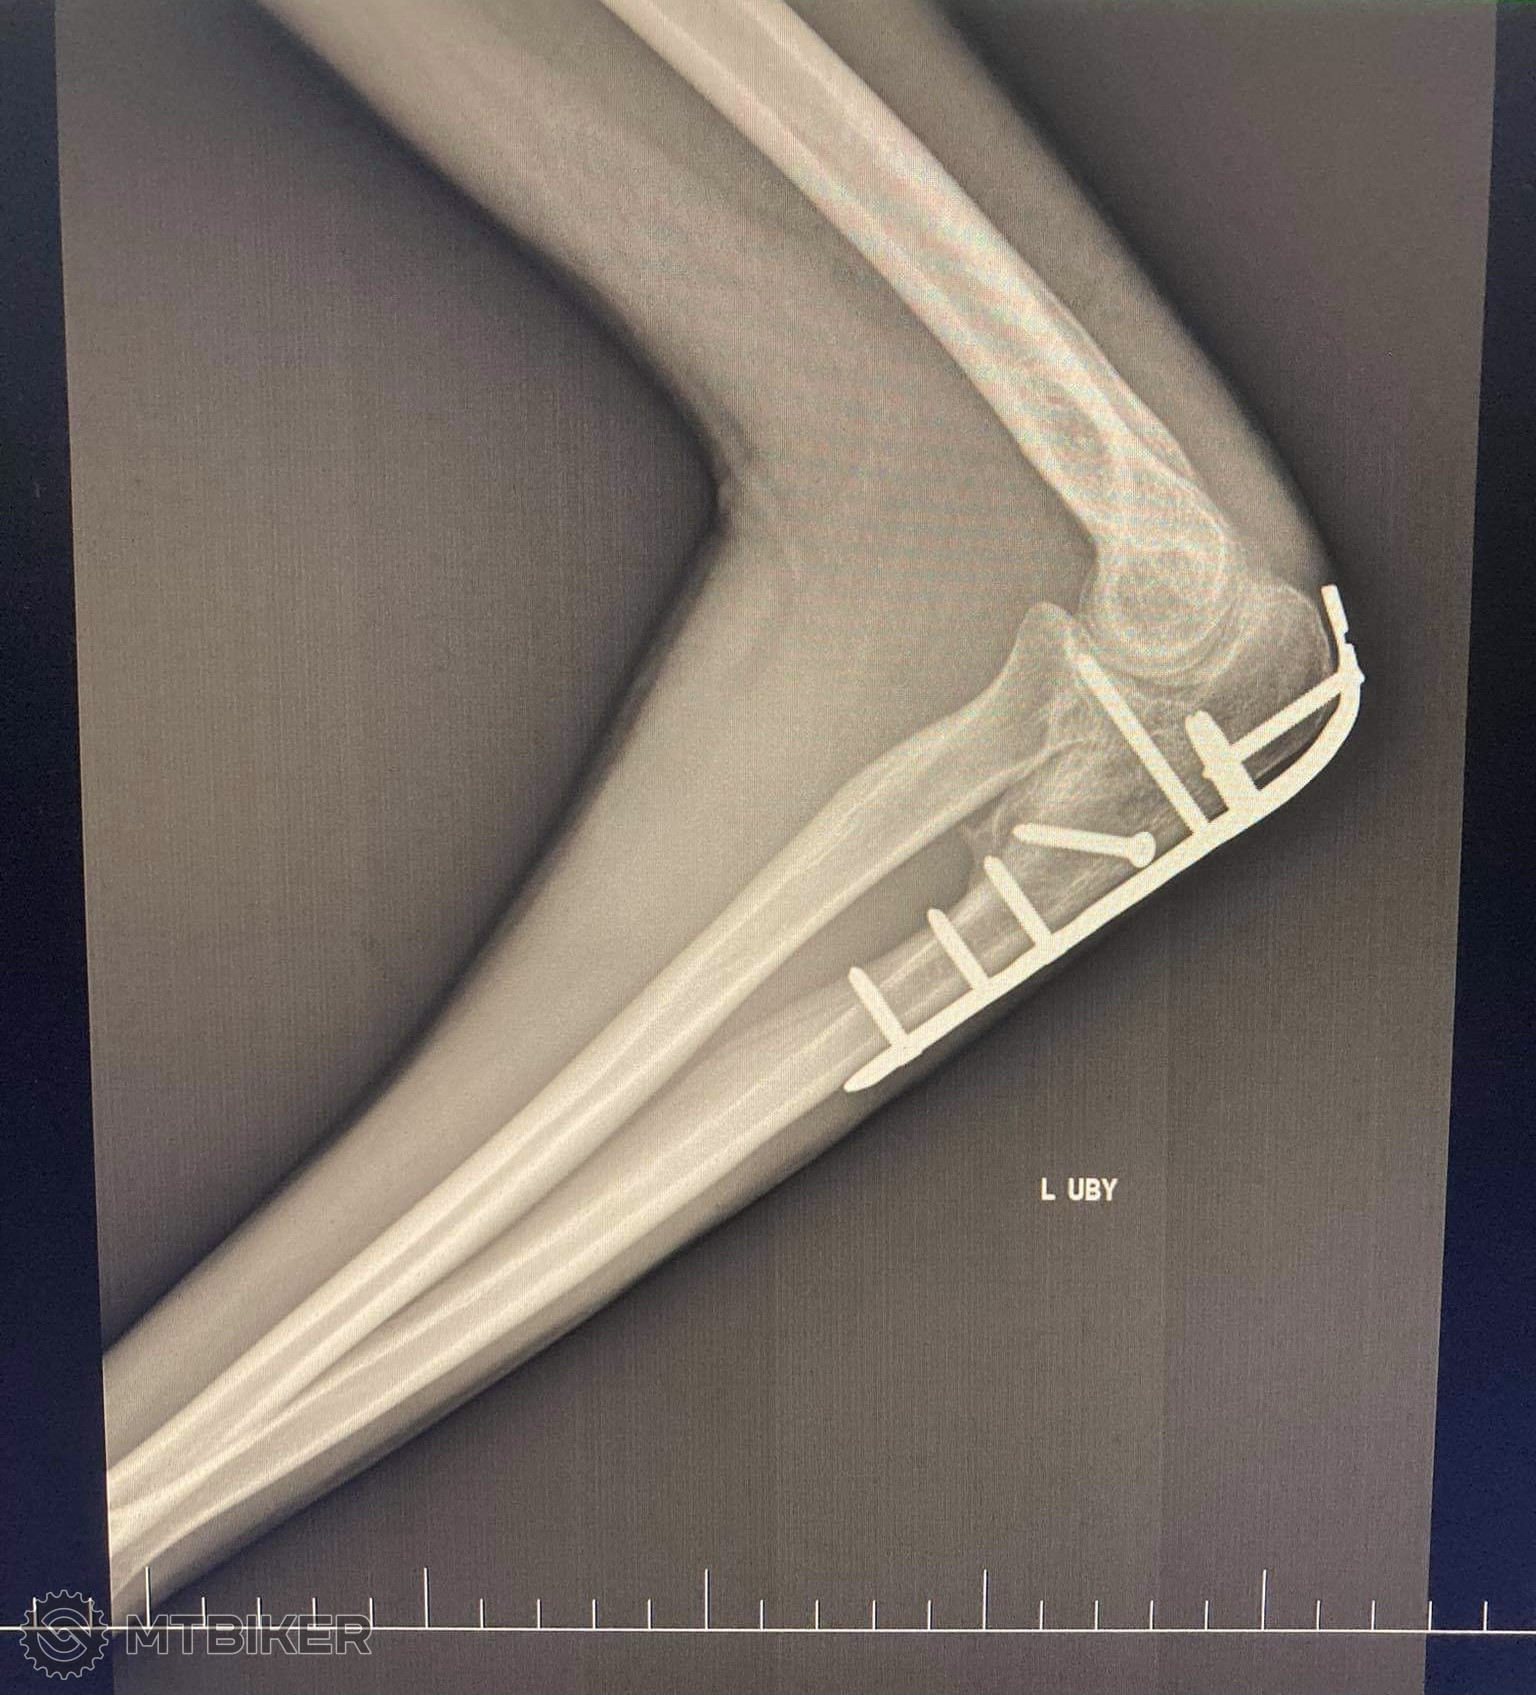

Ja som mal presne to iste. Jeden primar povedal konzervativna liecba ale ked sa to nelepsilo tak som si vybavil operaciu a vobec nelutujem. Spravili mi plastiku uponu prsneho svalu nakolko som si ho odtrhol. Odvtedy zastavam nazor ze vsetky zranenia riesit cim skor. Od vtedy uz 2 dalsie operacie /sroby a dlahy/ a vsetko bez problemov. Operacie vobec nelutujem.

Kaper ta snimka rtg napravo na monitore to mas zlomeny krcok stehennej kosti ? Ako sa ti dari, ako sa to hoji?